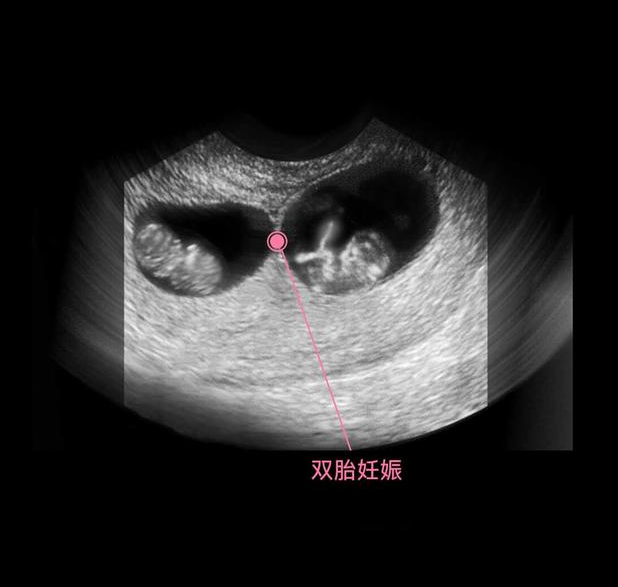

在上图可见是个双胎妊娠,胎儿具有一个很大的头,和身材很不对称,是不是跟出生后的胎宝宝有点像了?其实此时的头部比例更悬殊,宝宝的额面部器官发育很明显,心脏也开始了跳动,出现了胎心,此时做B超,可见震了厘胎心胎芽。